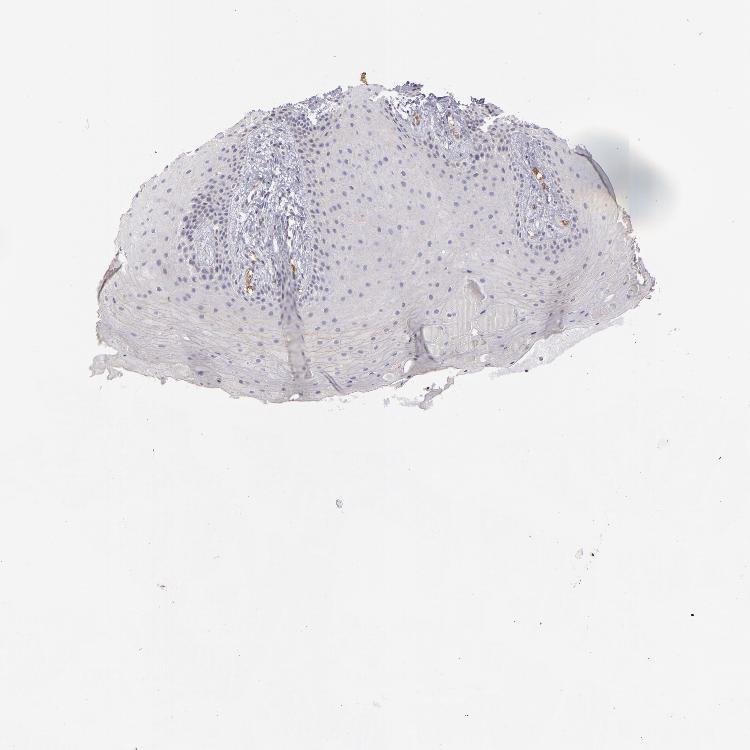

TISSUE PRIMARY DATA ORAL MUCOSA Show tissue menu

Oral mucosa

ORAL MUCOSA - Antibody stainingi

Antibody staining in the annotated cell types in the current human tissue is reported as not detected, low, medium, or high, based on conventional immunohistochemistry profiling in selected tissues. This score is based on the combination of the staining intensity and fraction of stained cells.

Each image is clickable and will lead to virtual microscopy that enables deeper exploration of all samples and also displays staining intensity scores, fraction scores and subcellular localization as well as patient and tissue information for each sample.

Antibody HPA029159Antibody HPA029160Antibody CAB000108Antibody CAB001950

Squamous epithelial cells HighHighMediumNot detected